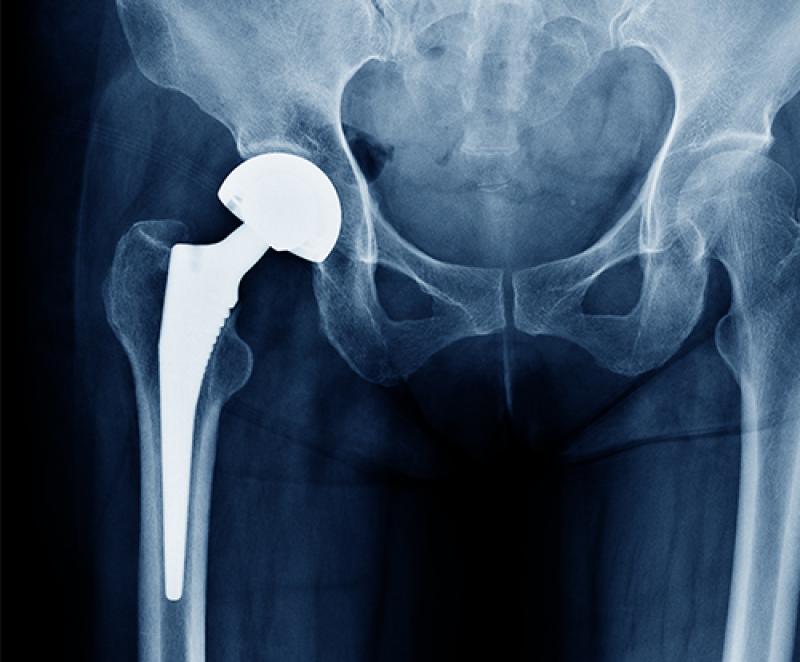

The Hip Implants Market is a vital component of the global orthopedic industry, providing essential solutions for individuals suffering from hip joint-related ailments such as osteoarthritis, fractures, and hip deformities. This market encompasses a wide range of hip implant devices, including hip resurfacing implants, total hip replacements (THR), and partial hip replacements. The demand for hip implants has been steadily increasing due to the aging population, rising prevalence of hip disorders, and advancements in implant materials and technologies.

One of the key factors driving the growth of the Hip Implants Market Size is the aging demographic worldwide. As the elderly population continues to grow, the incidence of hip-related conditions, particularly osteoarthritis, has surged. This has led to a higher demand for hip implant procedures to restore mobility and improve the quality of life for patients. Additionally, ongoing innovations in implant materials and design, such as the use of biocompatible materials and minimally invasive surgical techniques, have contributed to improved implant longevity and patient outcomes.